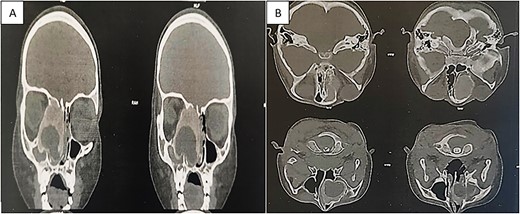

Flexible nasofibroscopy revealed a protrusion filling the right nasal fossa, closely approaching the nasal septum. Computed tomography (CT) and magnetic resonance imaging scans indicated a well-defined osteolytic lesion with a peripheral sclerotic rind, measuring 4.1 × 3.8 × 3.7 cm and originating from the right ethmoid, expanding into the ipsilateral nasal cavity, orbit, and maxillary sinus (Fig. 1).

CT showing an expansible, well-demarcated, osteolytic lesion with a peripheral sclerotic rind on the right side of the ethmoid bone, expanding into the ipsilateral nasal cavity, orbit, and maxillary sinus; (A) coronal CT scan; (B) axial CT scan.